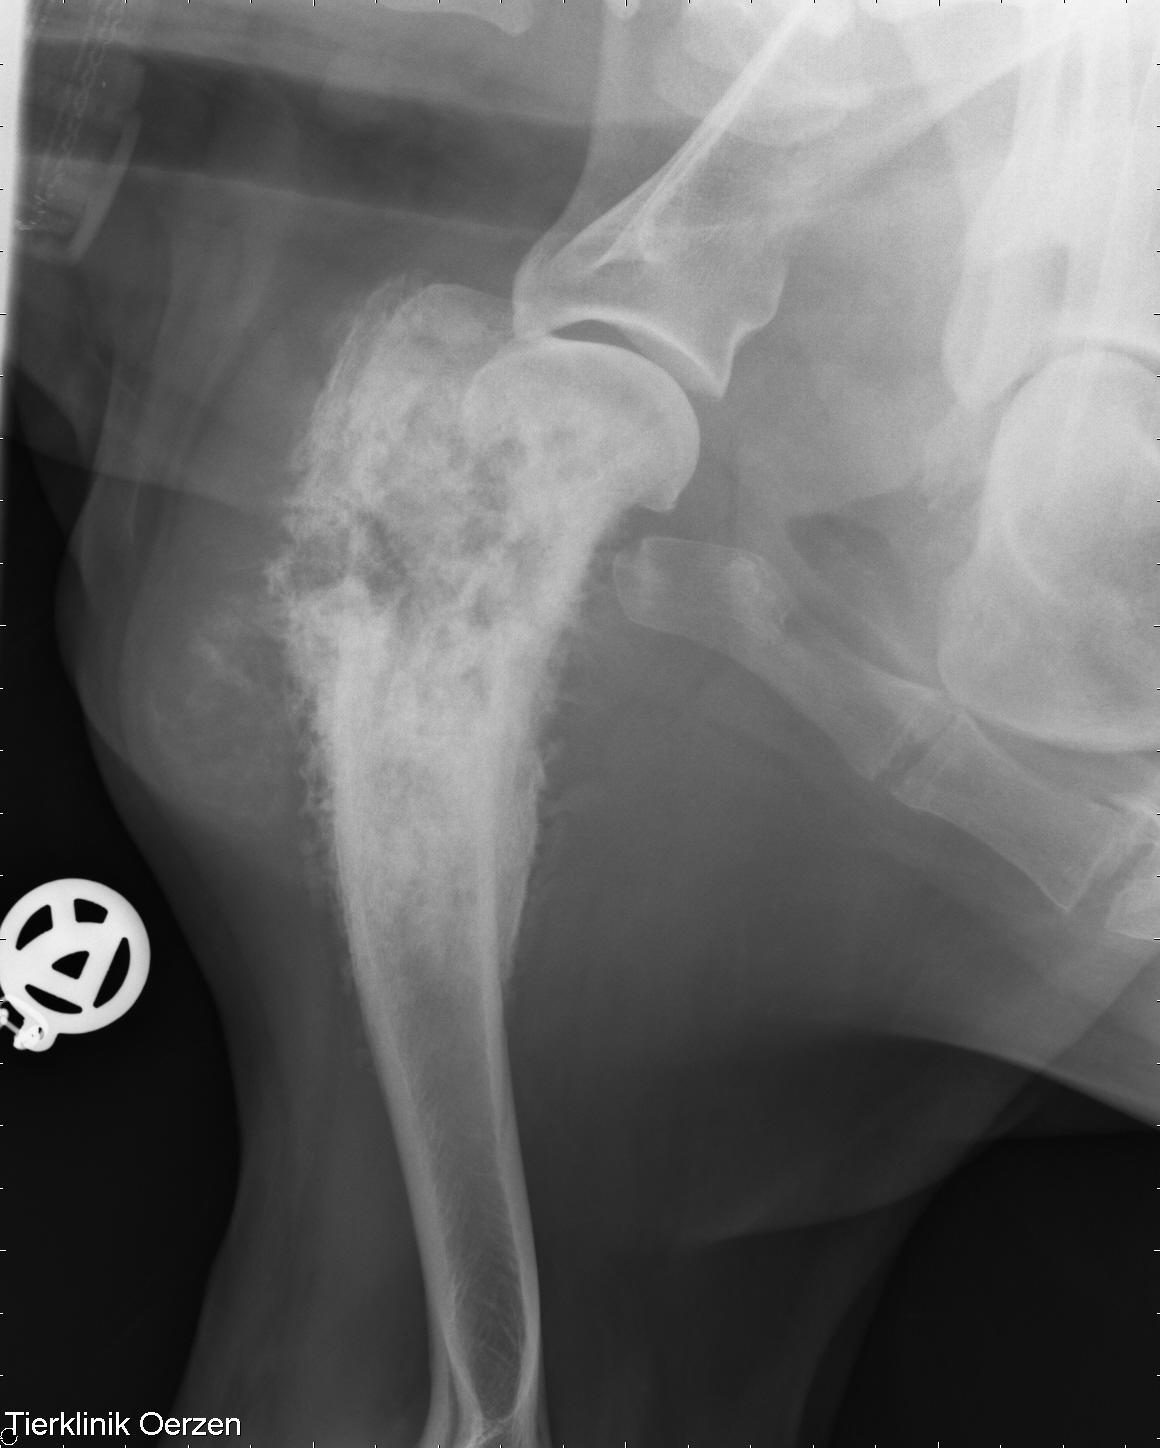

Details